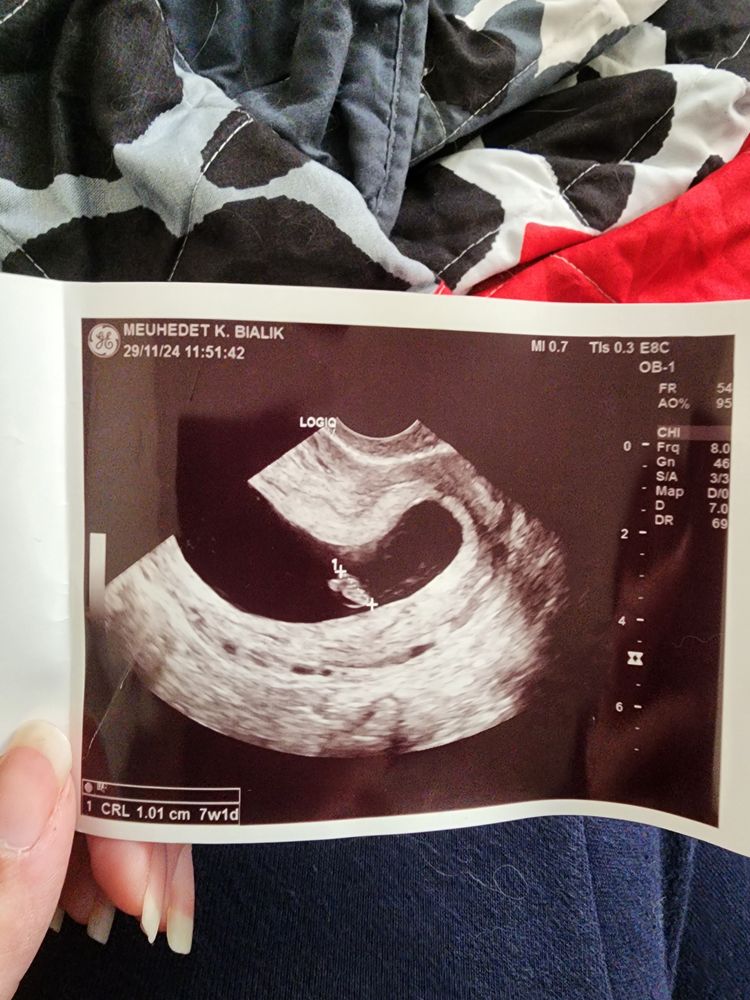

ludarabaev, Изображение Изображение

ludarabaev, это одно и то же плодное яйцо. И 2 эмбриона, которые отображаются по одному при разном выведении датчиком.

Ксения , я не думаю что у меня 2 эмбриона, потому что была у своего врача, у платного и в больнице..и все увидели 1 и не у кого нет ответа

Лара, я тоже была платно, реально там надо хорошо вывести, не всегда получается.

Настена, нет там никакой двойни , по узи картине четко видно один эмбрион

2 не видно, потому что датчик в нужной плоскости не попал

придется теперь ждать до 12 недель. сходите на узи через 2 недели в 9 недель и в 10 недель сдайте тест НИПТ